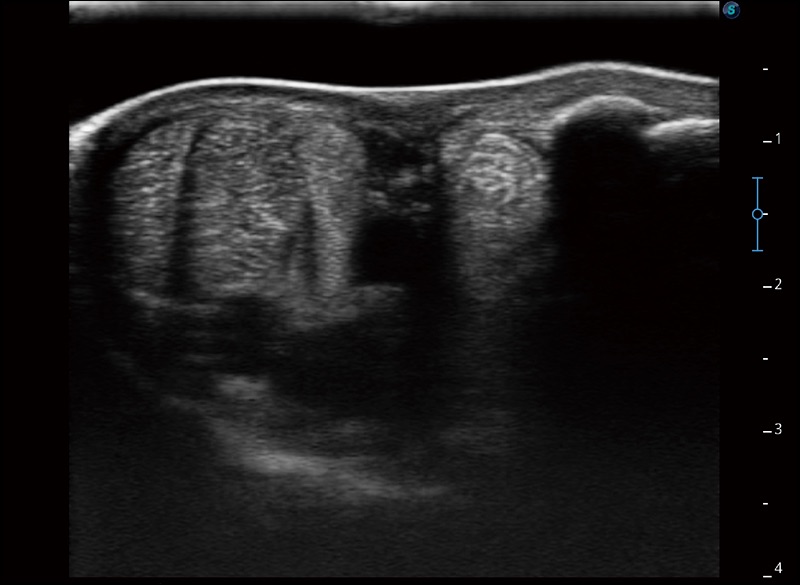

擴(kuò)展成像

支持線陣和凸陣探頭,一鍵操作即可獲得更寬的圖像視野